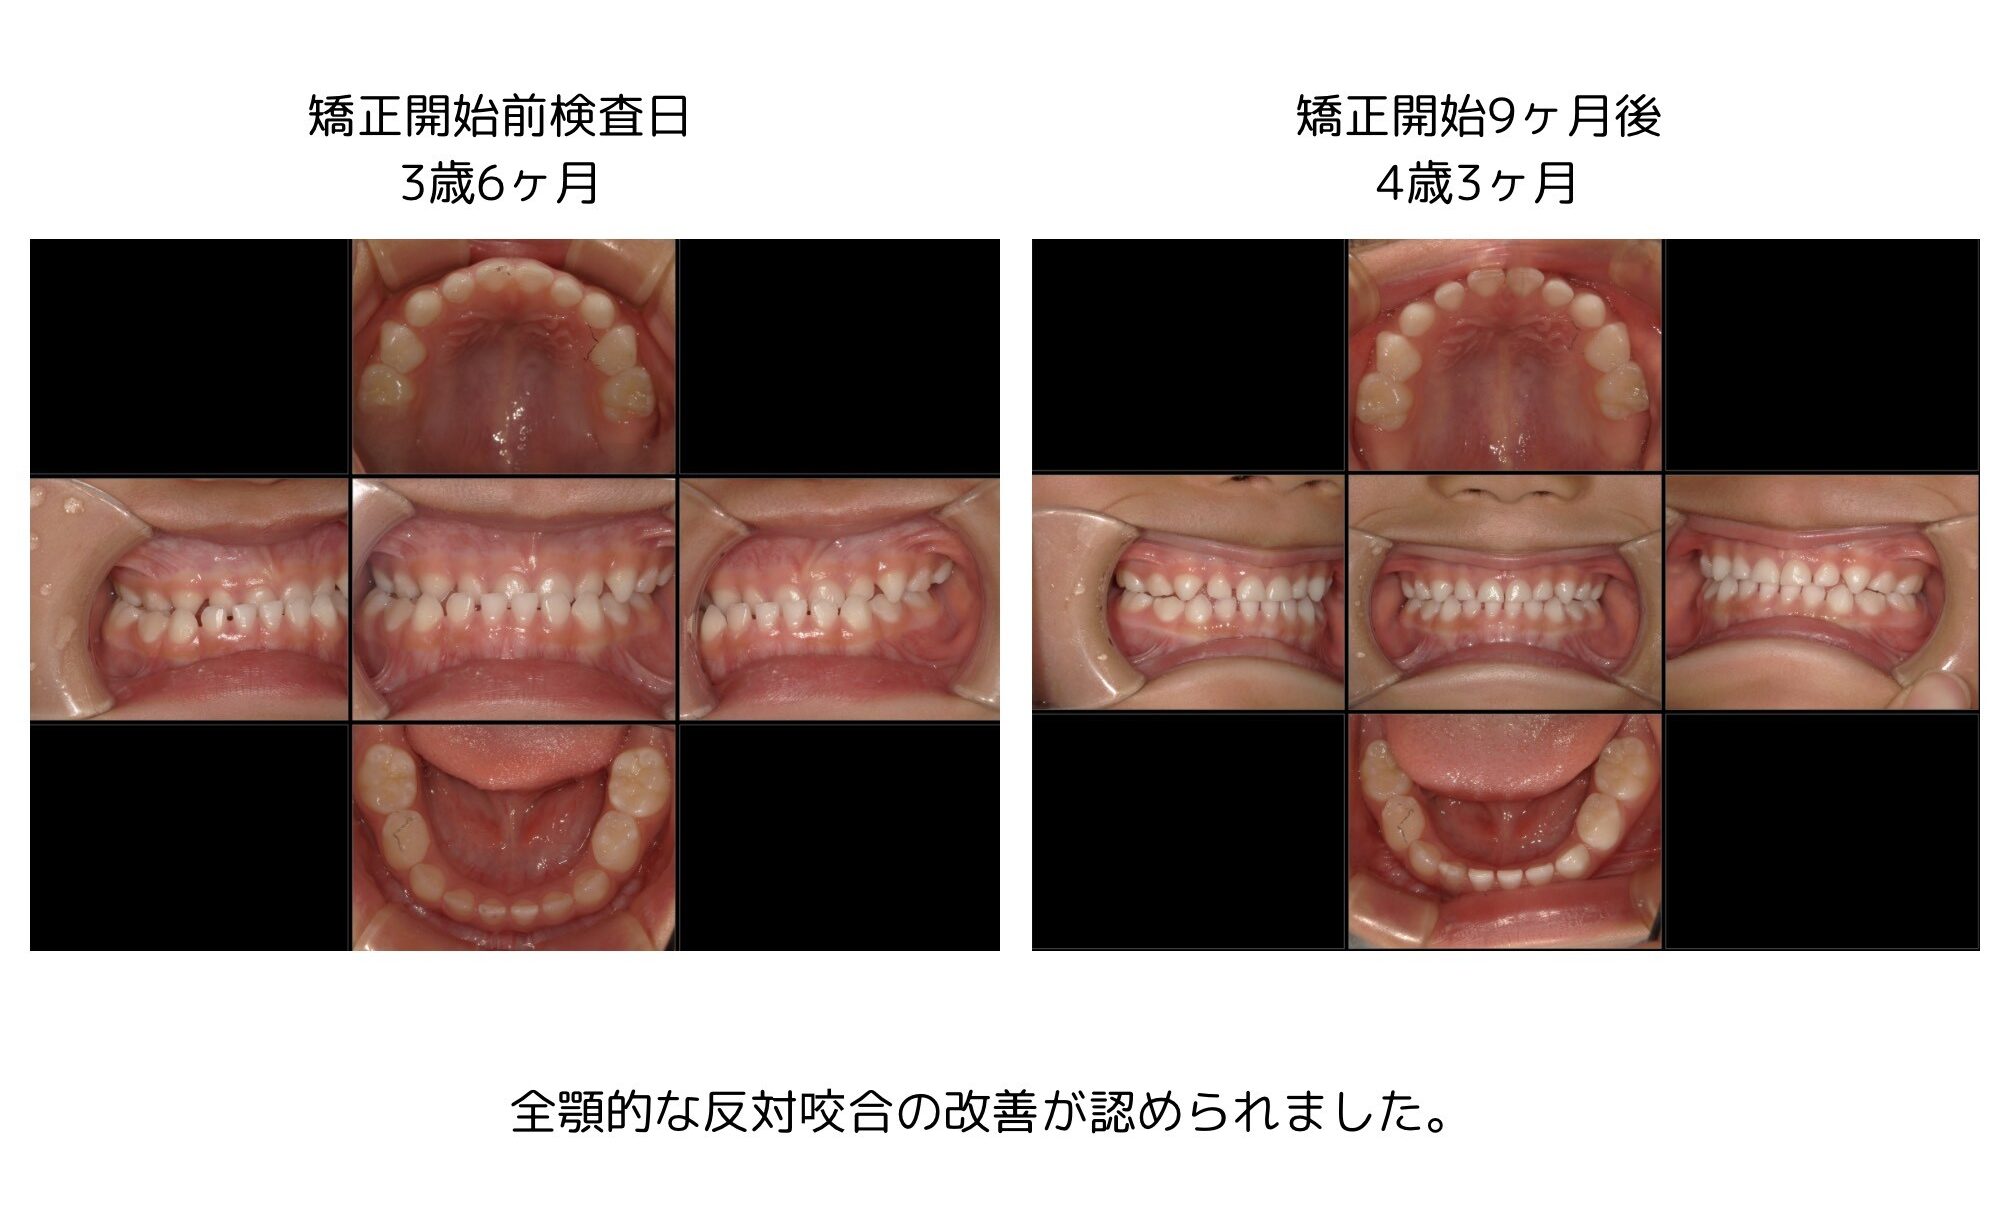

なおこ先生プロデュース 矯正用加熱振動装置。なおこ先生プロデュース 矯正用加熱振動装置 大人の矯正治療について。なおこ先生プロデュース 矯正用加熱振動装置 大人の矯正治療について。なおこ先生プロデュース矯正用加熱振動装置数回使用しましたがサイズが合わなく出品します。なおこ先生も動画でお伝えしておりましたが、振動によって矯正スピードアップを期待できる機器です。【内容】マウスピース、操作部(本体)、接続コード、取扱説明書●単4アルカリ乾電池×4本が必要です(内蔵してお届けします)【使用上の注意】次の方は使用しないでください。・口内の感覚が敏感な方・口腔または歯周手術の直後や治療中の方・口腔内に気になる症状(治療中の歯、不安定な入れ歯)がある方・歯ぐきからの出血が続く、または大量の出血がある方。矯正】上あごを広げる魔法の装置【固定式拡大装置】とは?? | ごとう。消毒済みです。【美品】AGE-R AIR SHOT(エアショット)。JOYトレ バーンコア。マウスピース矯正やワイヤー矯正をしたまま、矯正用加熱振動装置のマウスピースをくわえて、ご使用いただけます。大幅値下げ!パルティール シュアラインa(遠赤外線マット)。【パナソニック】バイタリフトかっさ EH-SP85-K。または使用を歯科医にご相談ください。リファ 4カラット(箱開封のみ)